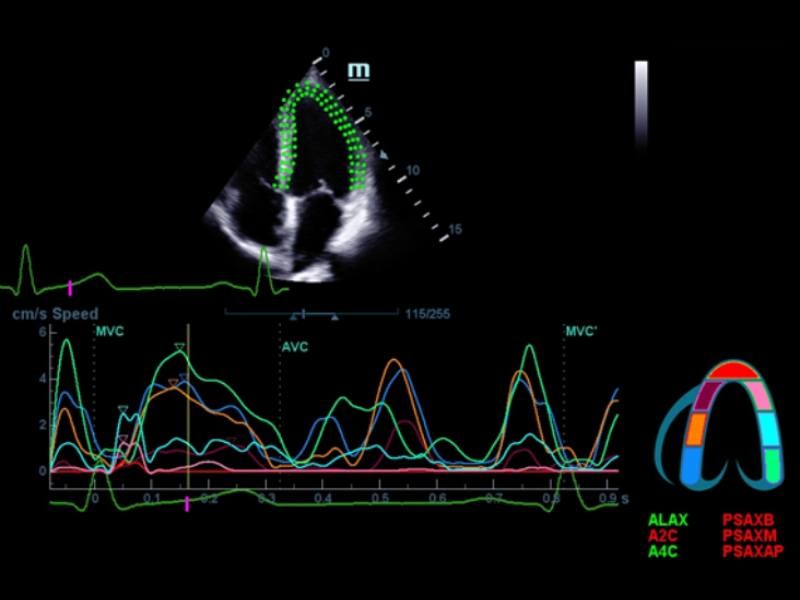

Iworks

O iWorks se beneficia dos protocolos integrados de varredura padrão para maior consistência e reduz o tempo do exame em até 50%. O poderoso e altamente flexível recurso fica ainda melhor com as capacidades definidas pelo usuário.